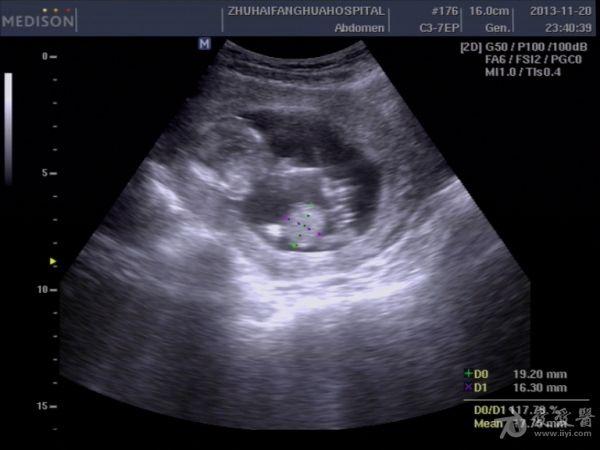

13周孕,24岁,初孕 因腹痛急诊***检查,是当天早上3点钟,医生提的黑白超,学生胆挺大的,超声图像如下:

学生直接诊断胎儿内脏外翻,上班后复查图像觉得问题不大,但还是被学生的胆大吓了一跳。这孩子连孕妇的联系方式都没留,人就放走了,今天终于联系上了孕妇,结果在市产院做的引产,结果同上。学生对我说,本来想诊断脐膨出的,觉得不像,还是像内脏外翻多些,大家说说,这孩子是该批评呢,还是该鼓励。我都有点哭笑不得了。